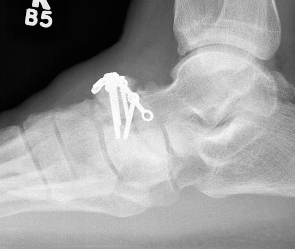

Xray

Displaced navicular stress fracture

Displaced stress fracture treated with single screw